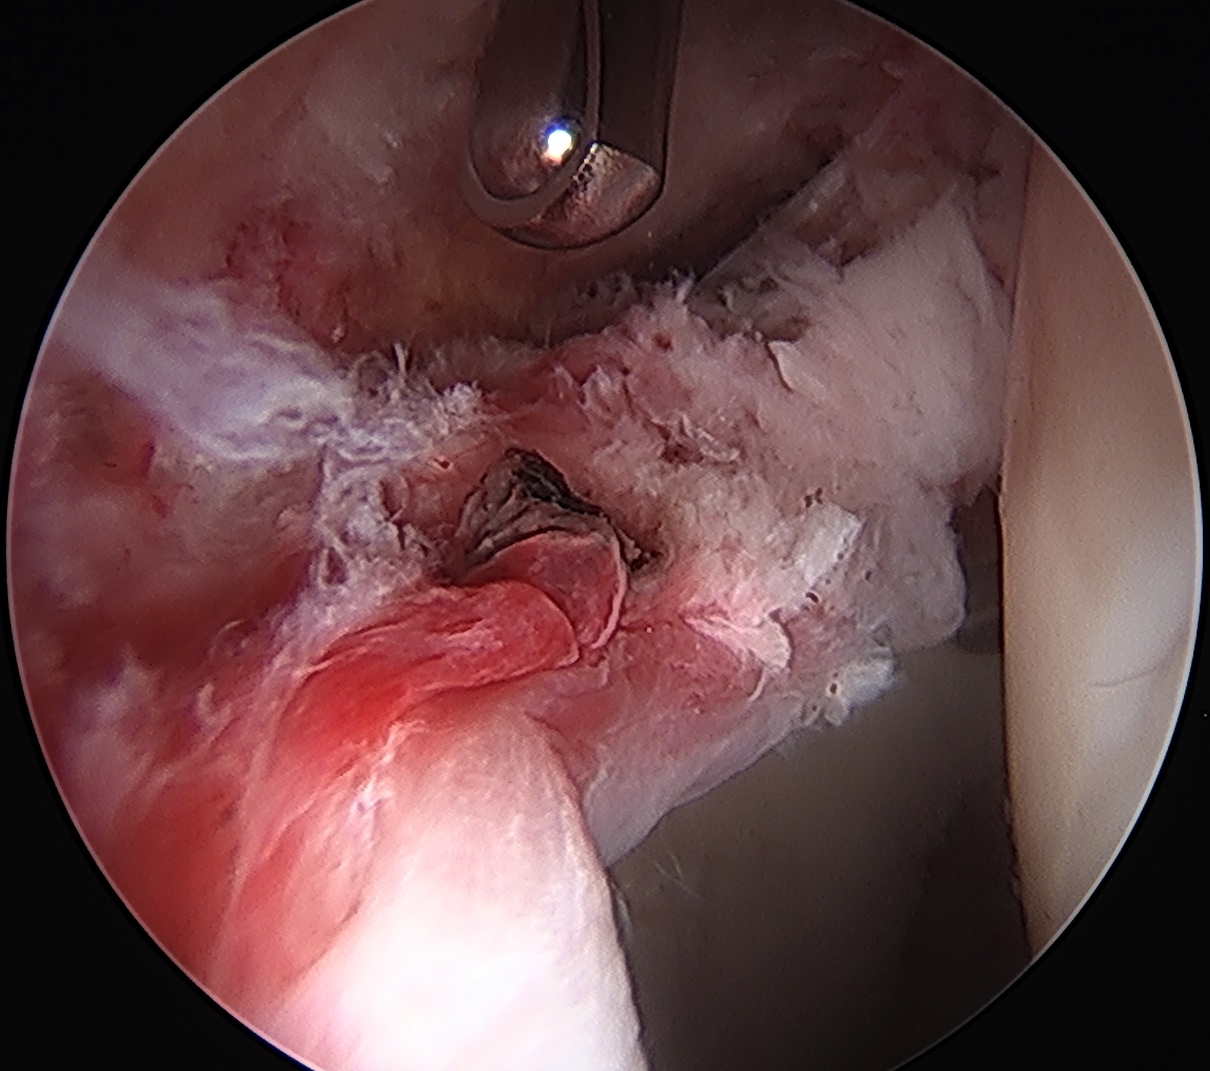

Labral debridement

- for degenerative / irreparable / ossified labrum / failed labral repair